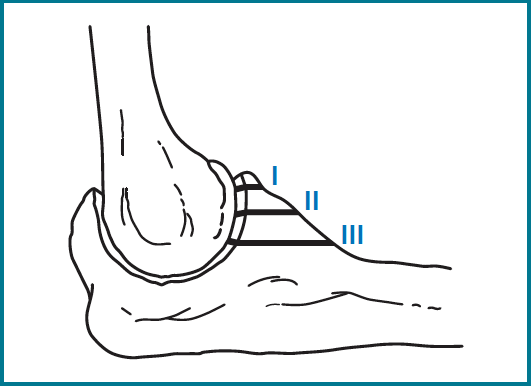

Regan y Morrey describieron 3 tipos de fracturas de coronoides según el tamaño del fragmento únicamente en el plano sagital. Las de tipo I son fracturas de la punta, las de tipo II las que afectan a menos del 50% de su altura y las de tipo III cuando el fragmento es mayor del 50% (Figura 1). Actualmente se usa la clasificación de O’Driscoll (Tabla 1), que la amplió teniendo en cuenta además la localización y el número de fragmentos (Figura 2)(3,4).